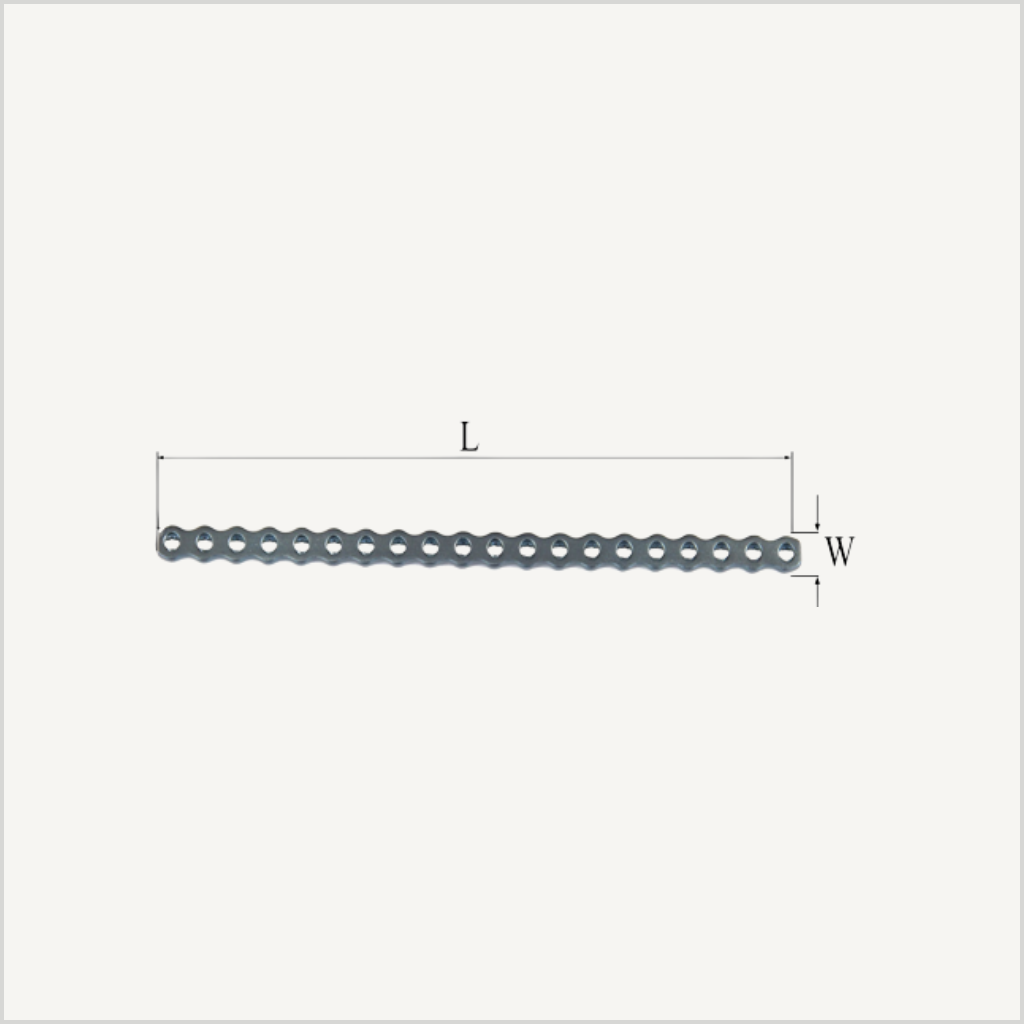

Implante PRCL Mini – 4mm (W) / 89.5 mm (L)

- Ancho del implante: 4mm

- Longitud: 89.5mm

- Agujeros: 20 agujeros

Implante PRCL Mini de 4 mm de ancho, 89.5 mm de longitud y 20 agujeros para el sistema PRCL Mini, diseñado para ofrecer una estabilización eficaz en procedimientos de cirugía ortopédica veterinaria.

Su diseño favorece una adaptación anatómica adecuada y una correcta distribución de cargas. Fabricado en material biocompatible, proporciona un rendimiento fiable y duradero en pacientes de pequeño tamaño.